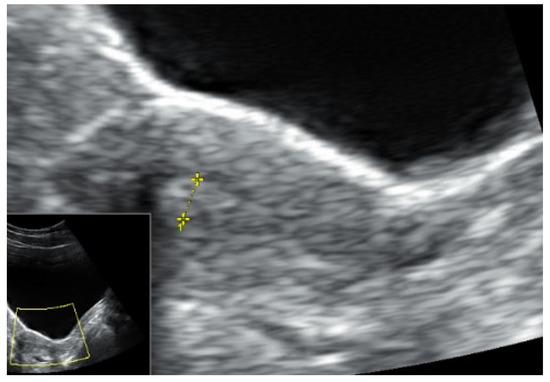

- Martire, F.G.; Lazzeri, L.; Conway, F.; Siciliano, T.; Pietropolli, A.; Piccione, E.; Solima, E.; Centini, G.; Zupi, E.; Exacoustos, C. Adolescence and Endometriosis: Symptoms, Ultrasound Signs and Early Diagnosis. Fertil. Steril. 2020, 114, 1049–1057. [Google Scholar] [CrossRef] [PubMed]